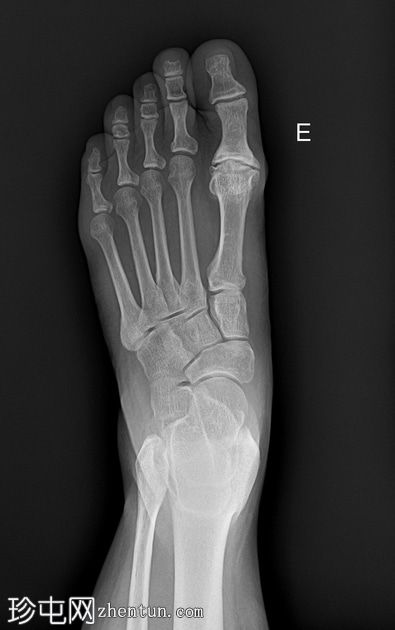

X线片

正位

第一跖趾关节可见巨大骨赘,关节间隙变窄。